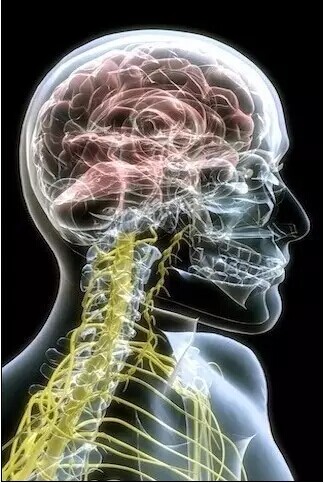

颈部脊柱、神经

头颅、颈椎

头颅

颈椎、大脑